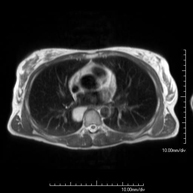

- RM Tórax

Prueba diagnóstica no invasiva que consiste en la obtención de imágenes de alta definición anatómica del tórax mediante el empleo de un campo electromagnético y ondas de radio (con un emisor y un receptor). No utiliza radiación ionizante. Está indicada en aquellas lesiones pulmonares en las que debe descartarse si existe infiltración del mediastino o de la pared torácica, para diferenciar si una lesión torácica es sólida o quística, etc. En ocasiones se deberá emplear contraste paramagnético (Gadolinio) para completar el estudio. - RM Abdomen

Prueba diagnóstica no invasiva que consiste en la obtención de imágenes de alta definición anatómica del mediastino mediante el empleo de un campo electromagnético y ondas de radio (con un emisor y un receptor). No utiliza radiación ionizante. El mediastino es la parte central de la caja torácica que incluye el timo, los grandes vasos (aorta torácica, vena cava inferior y superior, etc.), el corazón, la tráquea y los bronquios principales, ganglios linfáticos mediastínicos e hiliares, el esófago, etc. Está especialmente indicada en lesiones mediastínicas para diferenciar si son quísticas o sólidas, en el diagnóstico diferencial de las lesiones del mediastino anterior, etc. En ocasiones se deberá emplear contraste paramagnético (Gadolinio) para completar el estudio. - RM Tórax

Prueba diagnóstica no invasiva que consiste en la obtención de imágenes de alta definición anatómica del tórax mediante el empleo de un campo electromagnético y ondas de radio (con un emisor y un receptor). No utiliza radiación ionizante. Está indicada en aquellas lesiones pulmonares en las que debe descartarse si existe infiltración del mediastino o de la pared torácica, para diferenciar si una lesión torácica es sólida o quística, etc. En ocasiones se deberá emplear contraste paramagnético (Gadolinio) para completar el estudio. - RM Pared Torácica